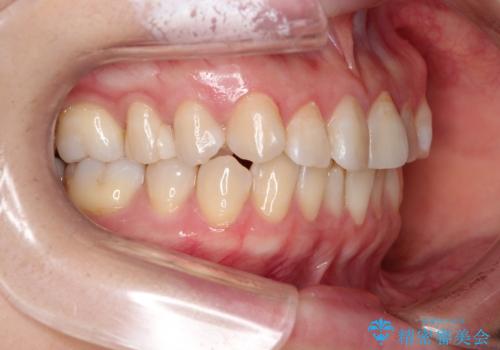

【インビザライン 】前歯の凸凹をなおしたい

- 前歯の凸凹を主訴に来院されました。

インビザライン にて治療を行い、歯並びが綺麗になったと満足していただきました。

前歯のガタガタの量が多かったため、IPR(歯のサイズを小さくするための処置)を行なって治療しました。